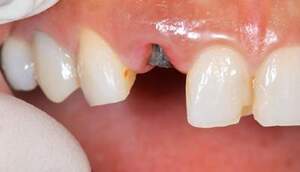

義歯の人工歯が磨耗に伴う、前歯の破折

長年使ってきた義歯の人工歯が磨耗し、臼歯部での咬合がすくなくなり、前歯部での接触が強くなったことで生じた前歯の破折なので、義歯も作り変える必要があります。 |

治療前で残存歯質がほとんどみられません。

残存歯質はないが、歯根は長いことを確認。